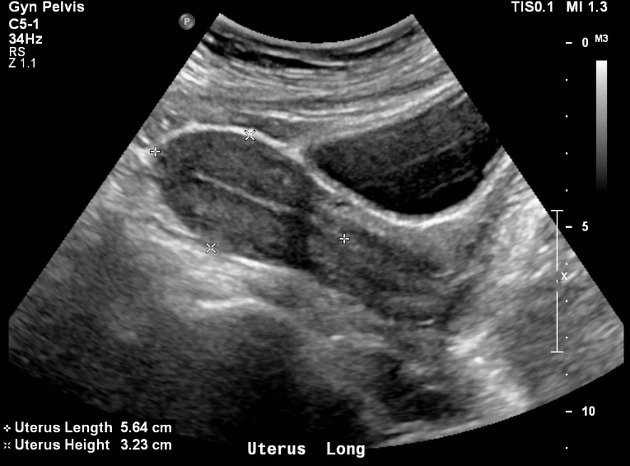

Siêu âm là một trong những bước quan trọng được sử dụng trong thăm khám phụ khoa. Phương pháp này giúp các bác sĩ đánh giá tình hình phát triển của các cơ quan sinh dục và phát hiện những bất thường. Vậy siêu âm có phát hiện viêm cổ tử cung không? Hãy cùng các chuyên gia giải đáp chi tiết qua nội dung bài viết sau đây.

Dựa vào hình ảnh siêu âm trên màn hình, các bác sĩ phụ khoa sẽ đánh giá tình trạng cơ quan sinh dục và đưa ra chẩn đoán và phát hiện bệnh phụ khoa nếu có. Do đó, siêu âm phụ khoa là phương pháp không thể thiếu trong quy trình thăm khám phụ khoa.

Siêu âm ổ bụng sử dụng đầu dò di chuyển quanh ổ bụng bên ngoài bề mặt da. Qua hình ảnh siêu âm có thể quan sát được độ dày niêm mạc tử cung, sự phát triển của trứng hay phát biện các bệnh lý như u nang buồng trứng, u xơ tử cung.

Vậy siêu âm có phát hiện viêm cổ tử cung không? Các bác sĩ chuyên khoa cho biết: siêu âm là cách tốt nhất để chẩn đoán viêm cổ tử cung ở nữ giới. Thông thường, chị em sẽ được chỉ định thực hiện một số xét nghiệm như siêu âm ổ bụng, xét nghiệm vi trùng học huyết trắng lấy từ dịch cổ tử cung để tìm hiểu nguyên nhân gây bệnh.

Trên thực tế, siêu âm có thể giúp tầm soát và phát hiện bệnh viêm cổ tử cung cũng như khối u cổ tử cung nếu có, dựa vào hình ảnh siêu âm.